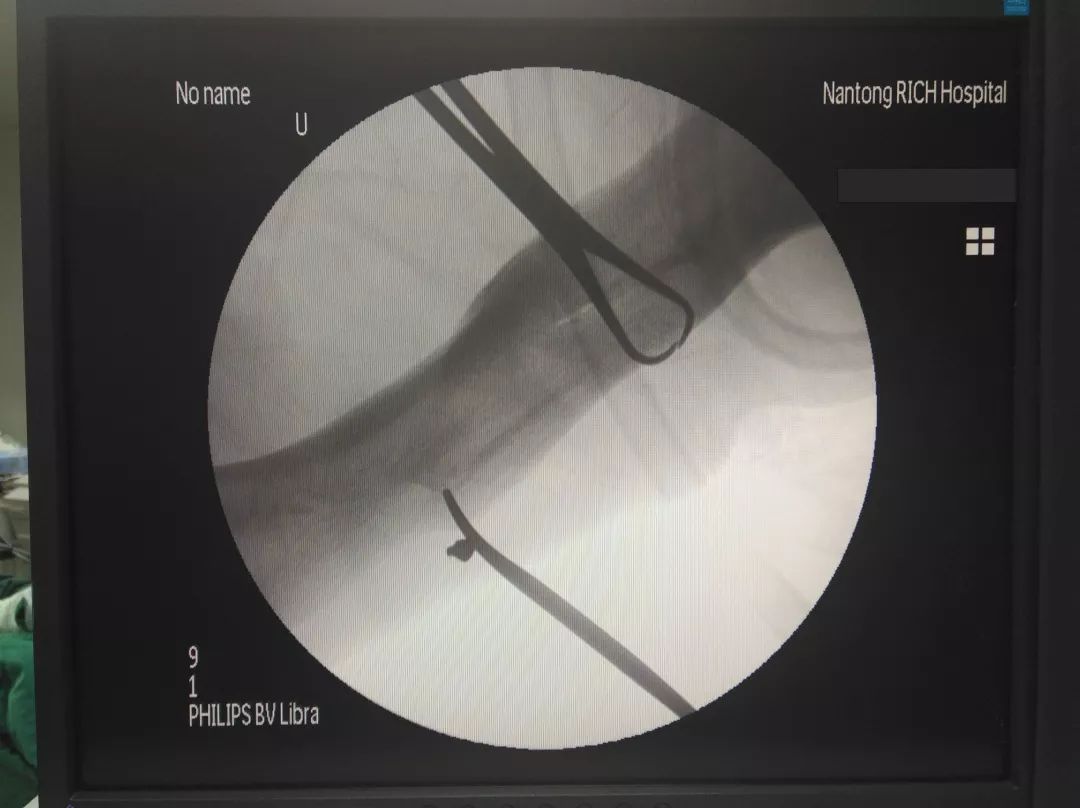

王瑞良主任正在取彈片

由于彈片殘留時(shí)間過長,被疤痕以及血管、神經(jīng)等組織緊緊包裹著,手術(shù)有一定難度。在王主任和醫(yī)護(hù)人員的共同努力下,經(jīng)過半個(gè)多小時(shí)的手術(shù),碎彈片終于被取了出來,兩塊彈片拼在一起約4mm乘以5mm大小,屬于彈尖部分。術(shù)后,王主任也對(duì)老郭右臂進(jìn)行了康復(fù)性檢查,手臂活動(dòng)正常,手術(shù)非常成功。